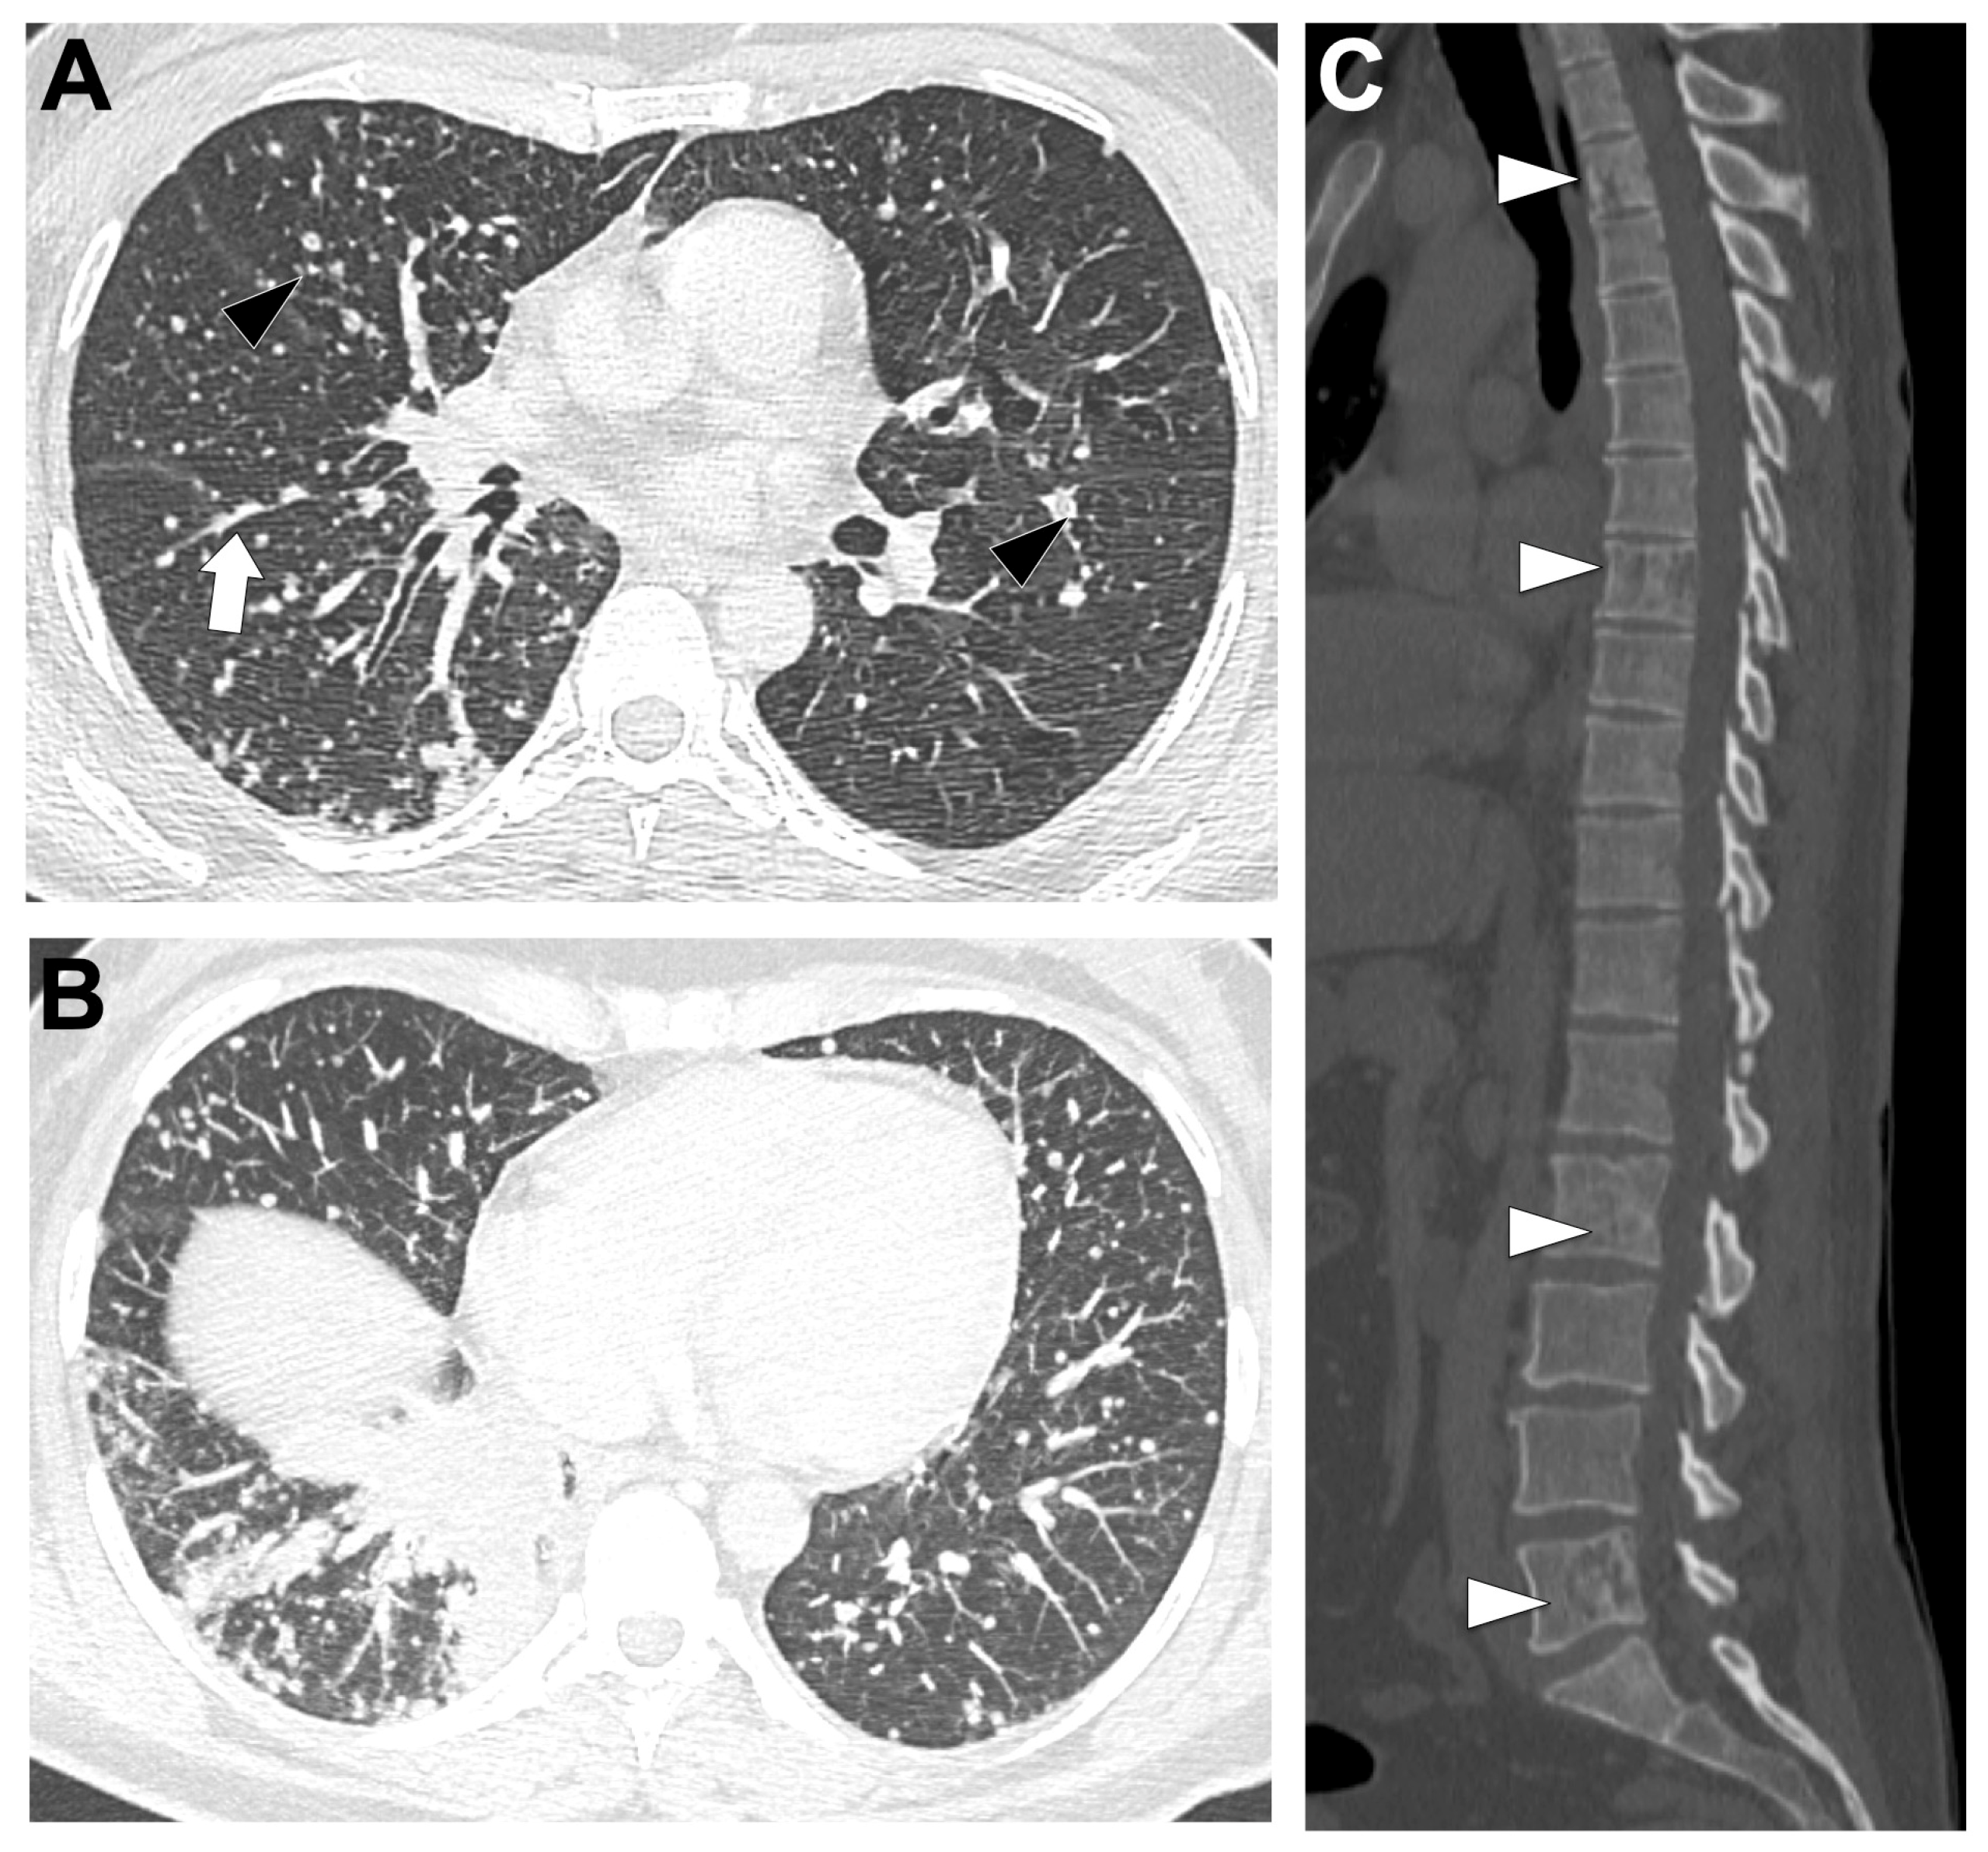

3.6. MET Exon 14-Altered NSCLC (Figure 6)

3.6.2. Radiological Characteristics of the Primary Lung Lesion in MET Exon 14-Altered LUAD

3.6.3. Metastatic Pattern in MET Exon 14-Altered LUAD